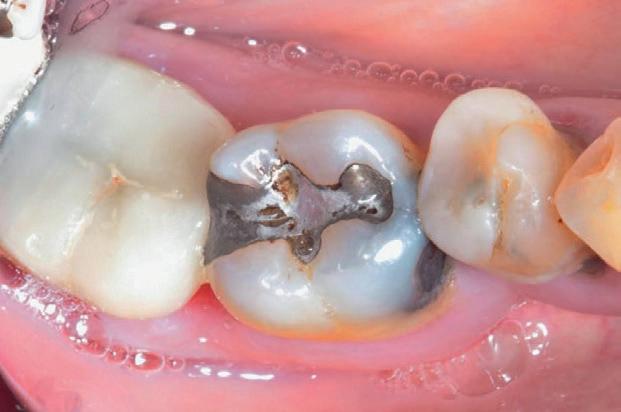

Un pacient caucazian în vârstă de 77 ani s-a prezentat la clinica autorului după cinci ani în care nu a fost la niciun control stomatologic. Examinarea clinică a arătat o pierdere semnificativă de os, parodontită cronică și multiple edentații care au destabilizat ocluzia. Pacientul a raportat sensibilitate la rece la nivelul primului molar drept inferior nr. 46, în special la ingerarea de lichide reci. Radiografia periapicală a confirmat constatările examenului clinic; în

plus, s-a detectat și prezența unei carii radiculare la nivelul rădăcinii distale a aceluiași molar, cu răspuns pozitiv la testul de sensibilitate (fig. 1-2).

Planul de tratament a început cu accent pe restabilirea sănătății parodontale. Într-o ședință ulterioară, odată cu îmbunătățirea stării parodonțiului, s-a efectuat restaurarea molarului nr. 46. Sub anestezie la Spina Spix pe partea dreaptă și

Figurile:

1. Situația clinică inițială.

2. Radiografia inițială.

3. Cavitate de clasa a II-a preparată.

4. Septomatrix pe poziție.

5. Cavitatea profundă.

izolarea cu digă de cauciuc, restaurarea din amalgam a fost îndepărtată complet și s-a obținut accesul la cavitatea carioasă (fig. 3-5). În ciuda proximității față de țesutul pulpar, nu a avut loc nicio expunere, iar cavitatea de clasa a II-a a fost restaurată complet cu Biodentine™ (fig. 6-8).